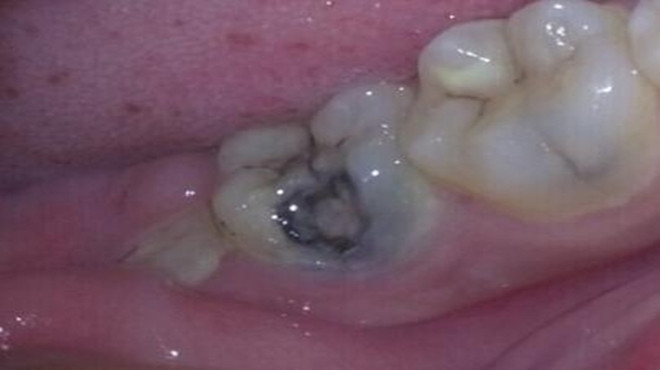

很多人因为常吃甜食或是过于刺激的食物,而没有及时刷牙,又或是晚上没有养成刷牙的好习惯,时间久了导致口腔内细菌的滋长,就可能诱发牙齿疾病。一般蛀牙就是这样生成的,牙齿表面出现黑色的小洞,若任其发展,小洞就会越来越大,吃饭塞牙,最终疼痛难忍。

蛀牙严重后会伤害到牙髓,到时候就会引发牙髓炎、根尖周炎等感染疾病,治疗起来就会更加的费事了,需要的时间与金钱也会增加很多。

蛀牙会带来疼痛,平时可能没啥感觉,但是只要一吃食物牙齿就会疼的厉害,久而久之就会造成偏嚼的习惯,让整个面部看起来都不协调,而且蛀牙如果发生在前牙,张口就是一个黑洞,那该多难看啊。